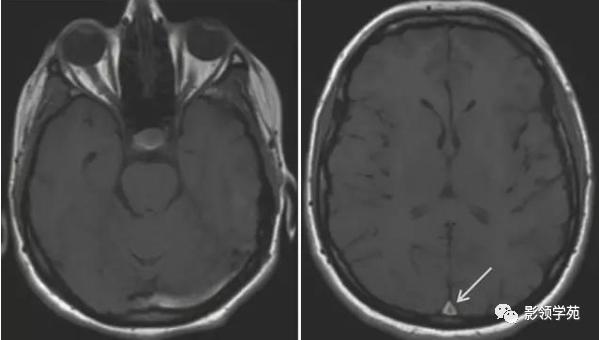

图 2 左图为左侧乙状窦血栓;右图上矢状窦血栓

图 4 左图位于 Monro 孔胶样囊肿;中图为位于蝶鞍上颅咽管瘤;右图为 Rathke’s 裂囊肿